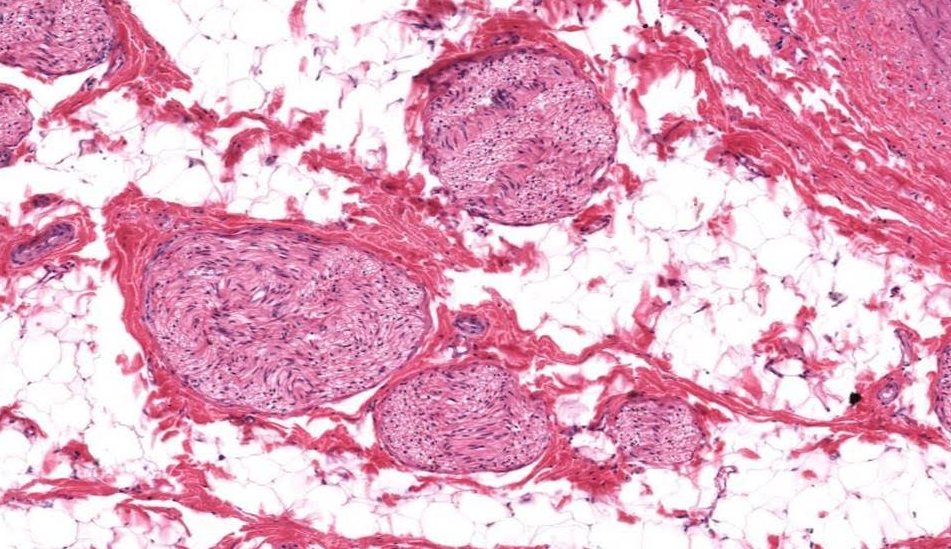

Túmulos seminiferos

Testículo

Células de Leydig